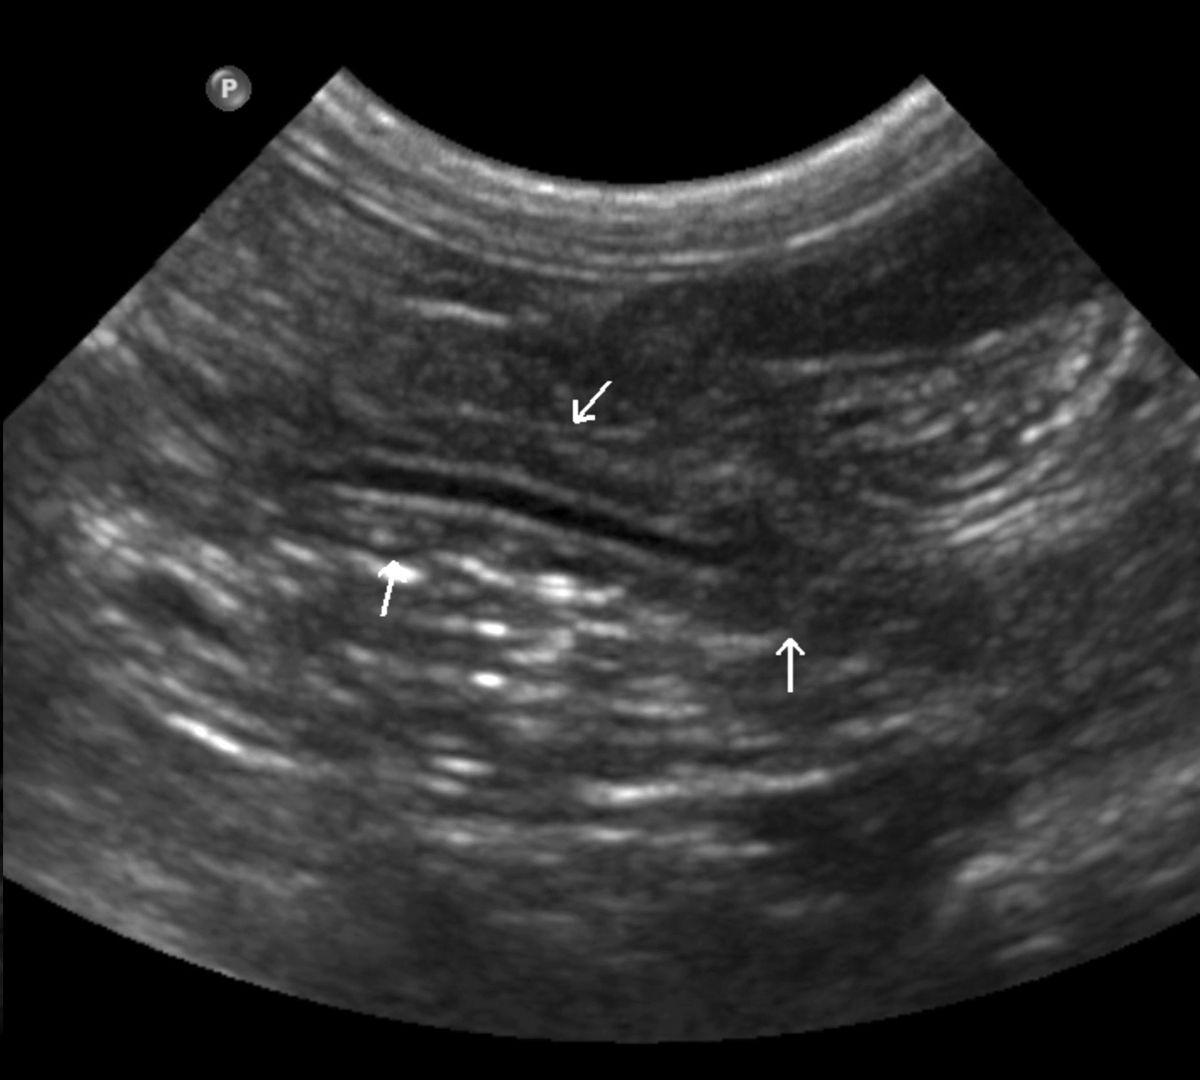

L'ecografia è utile per l'imaging del pancreas, sebbene la valutazione in modo accurato richieda una certa esperienza. Il pancreas normale è discretamente eterogeneo e di solito leggermente ipoecogeno rispetto al grasso circostante, con margini scarsamente definiti [3]. Può avere la stessa ecogenicità del grasso circostante nei gatti, e iperecogeno nello Yorkshire terrier [4]. La valutazione del pancreas si basa principalmente sull'identificazione di specifici punti di repere. Per valutare il lobo destro è importante identificare la porzione di duodeno che si estende dal rene destro, caudalmente, al piloro, cranialmente. Nel cane, la vena pancreatico-duodenale è una struttura anecogena tortuosa e tubolare facilmente identificabile, parallela alla faccia mediale del duodeno (Figura 6a); il tessuto circostante questo vaso è il pancreas. Il color Doppler può essere utile per localizzare meglio tale vaso. Nel gatto, in questa posizione si trova il dotto pancreatico, che aiuta a localizzare il lobo destro del pancreas. Il dotto pancreatico è fisiologicamente dilatato nel gatto (specialmente nei gatti anziani può arrivare fino a 3 mm di diametro) e si congiunge al dotto biliare comune a livello della papilla duodenale maggiore. Il corpo del pancreas è localizzato caudalmente rispetto al piloro e ventralmente alla vena porta, tra stomaco e colon trasverso. Il lobo pancreatico sinistro può essere visualizzato sull'aspetto laterale del colon discendente, caudalmente al fondus dello stomaco, medialmente alla milza, e cranialmente al polo craniale del rene sinistro. Anche il dotto pancreatico può aiutare a localizzare questo lobo nel gatto (Figura 6b). Nei gatti lo spessore del pancreas non deve superare il centimetro [5].

Ecografia di un pancreas normale (frecce bianche) in un gatto; il dotto pancreatico può aiutare a identificarlo.

Figura 6b. Ecografia di un pancreas normale (frecce bianche) in un gatto; il dotto pancreatico può aiutare a identificarlo.© Laurent Blond